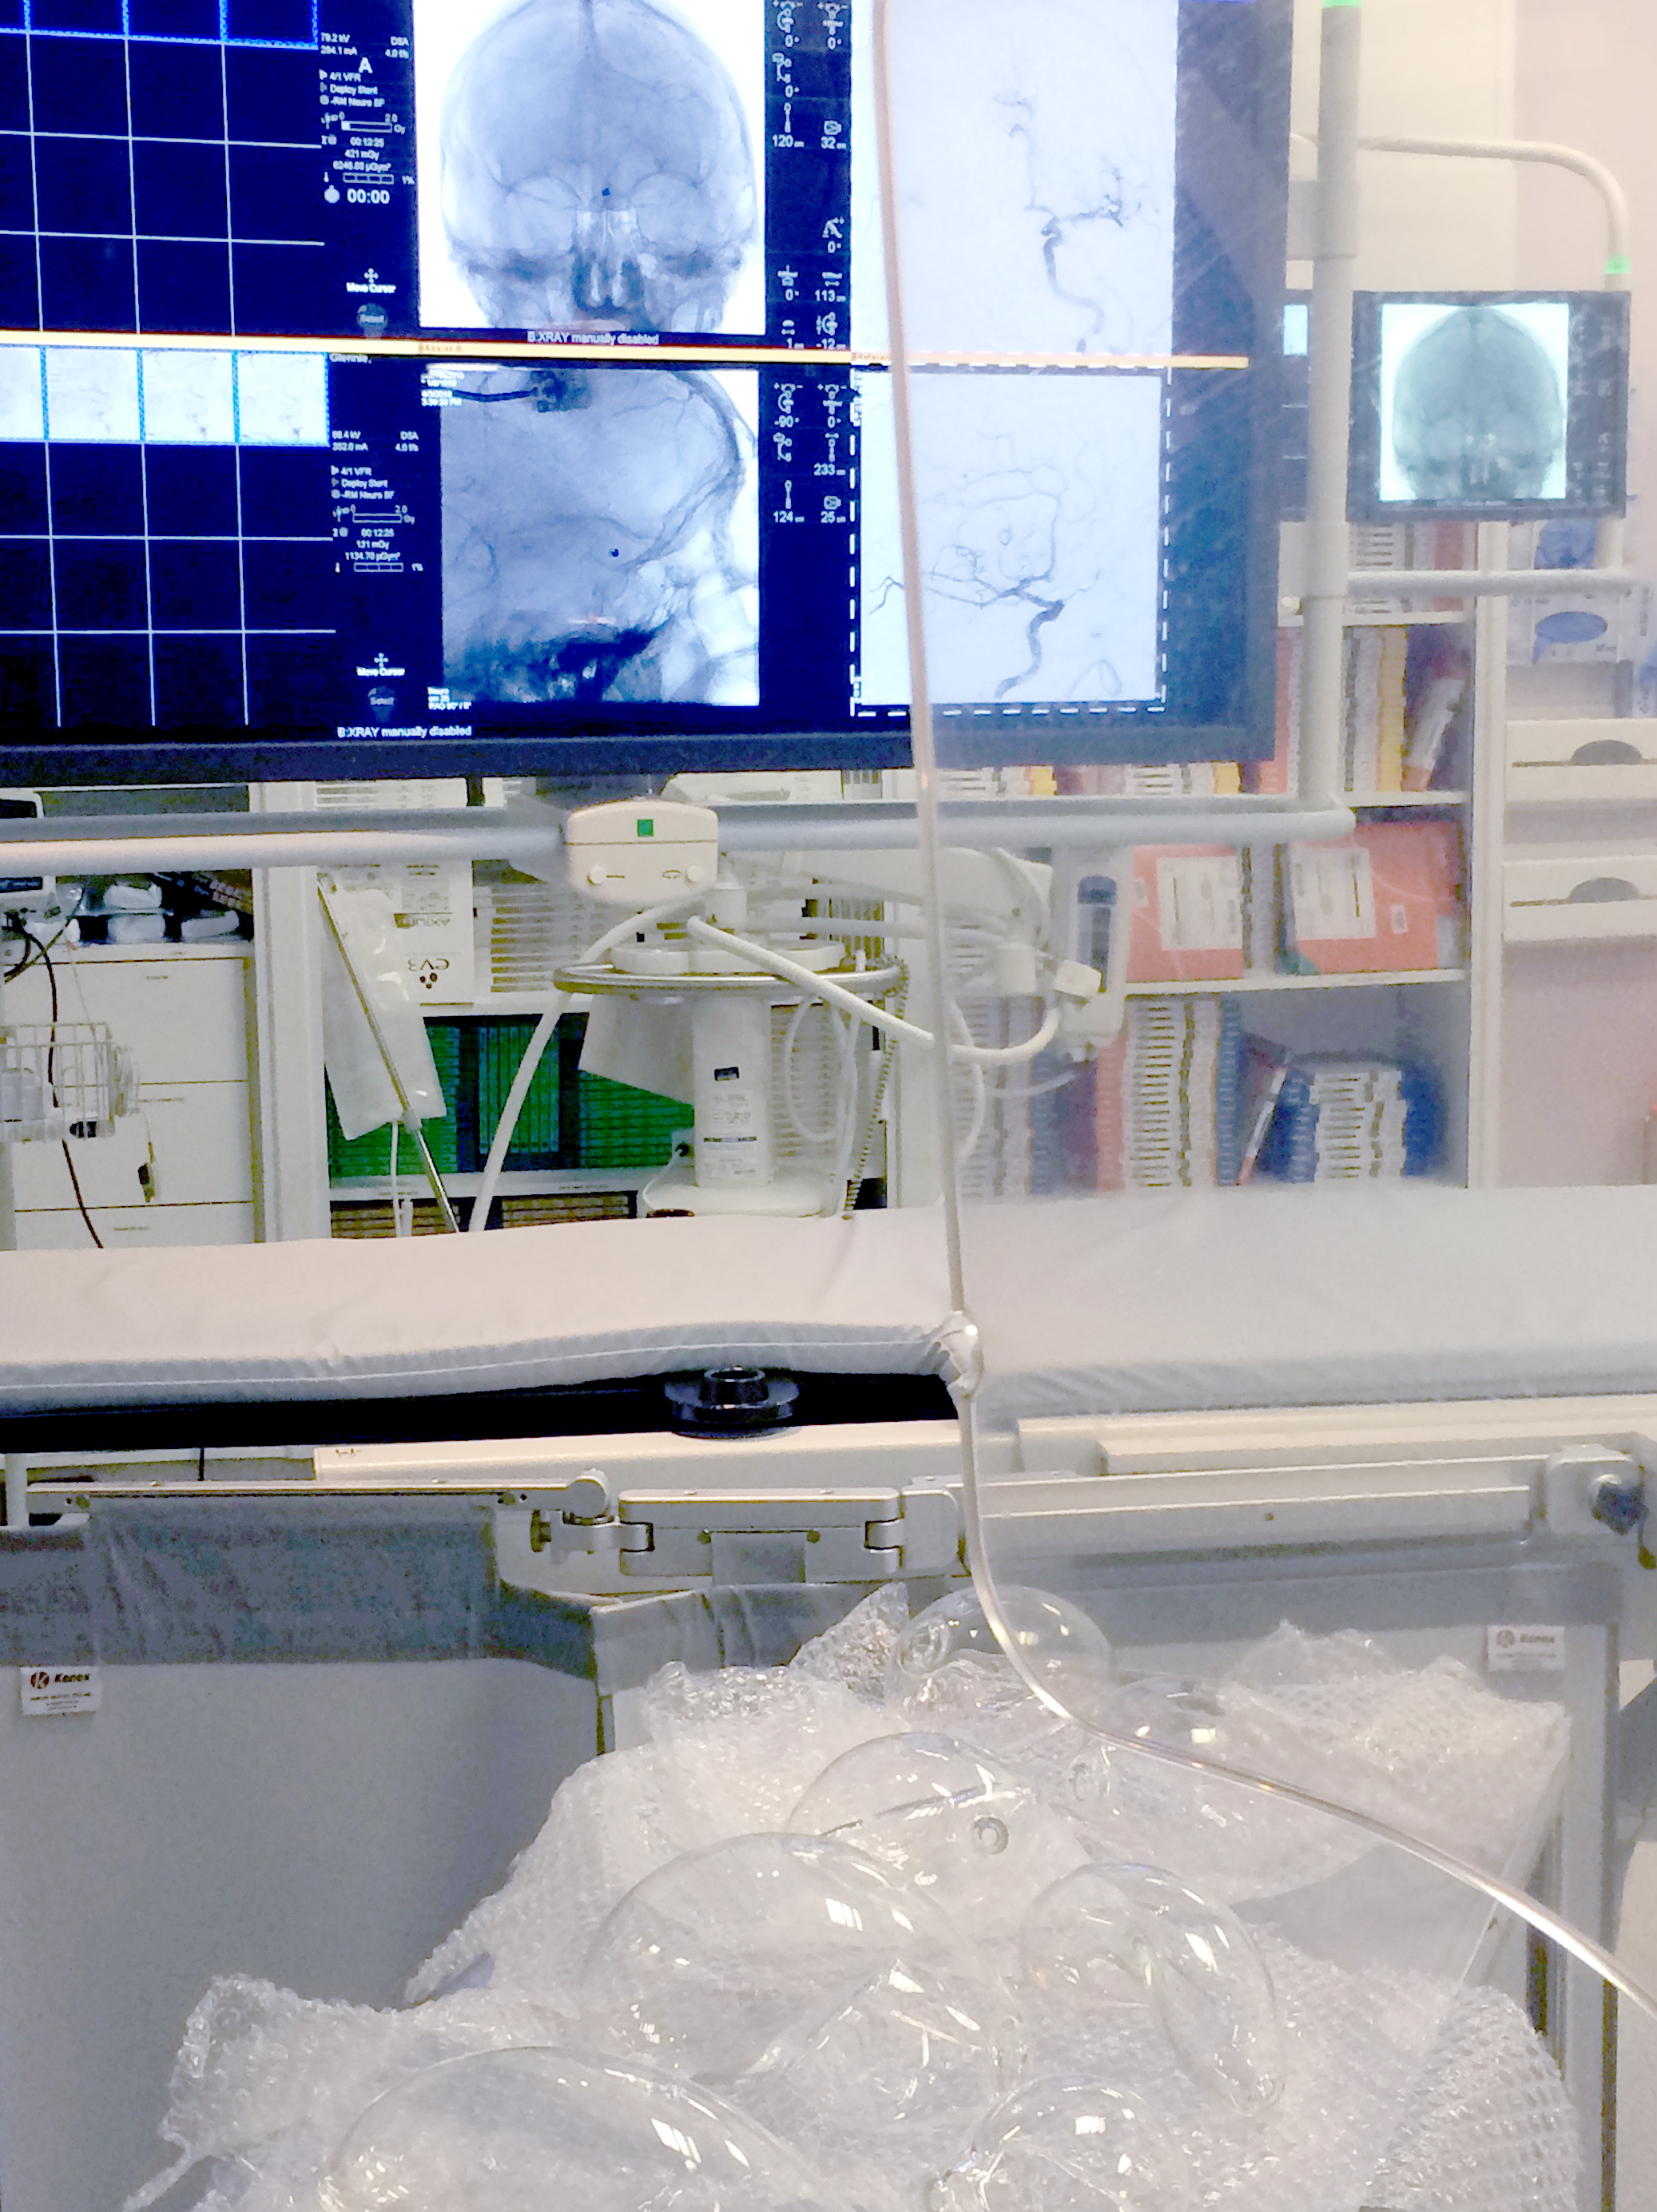

The research and work followed the treatment of tangled blood vessels in the brain, or arteriovenous malformations, through an embolisation procedure performed by the Neuroradiology team at Western General Hospital’s Department of Clinical Neuroscience. In this process, a glue-like substance is introduced into the brain which changes the smell of the breaths of both neuroradiologist and patient. As there is no “opening-up” of the body, the procedure leaves no visible scars and this so-called “Onyx smell”, which lingers in the wards after the intervention, is the only physical indicator of the operation that took place.